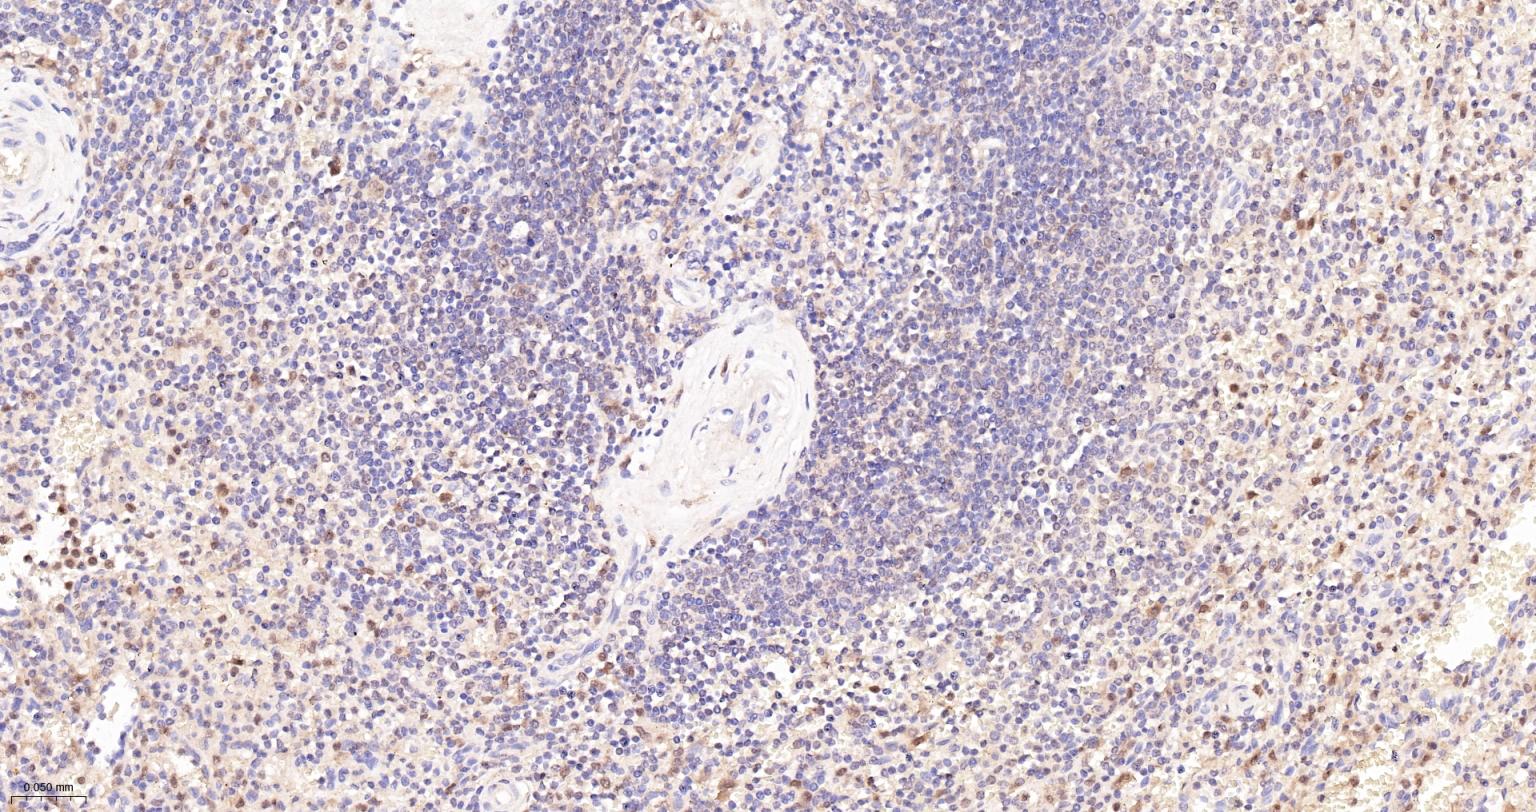

Paraformaldehyde-fixed, paraffin embedded Human Spleen; Antigen retrieval by boiling in sodium citrate buffer (pH6.0) for 15 min; Antibody incubation with ASC/TMS1 Monoclonal Antibody, Unconjugated(bsm-61273R) at 1:200 overnight at 4°C, followed by conjugation to the bs-0295G-HRP and DAB (C-0010) staining.